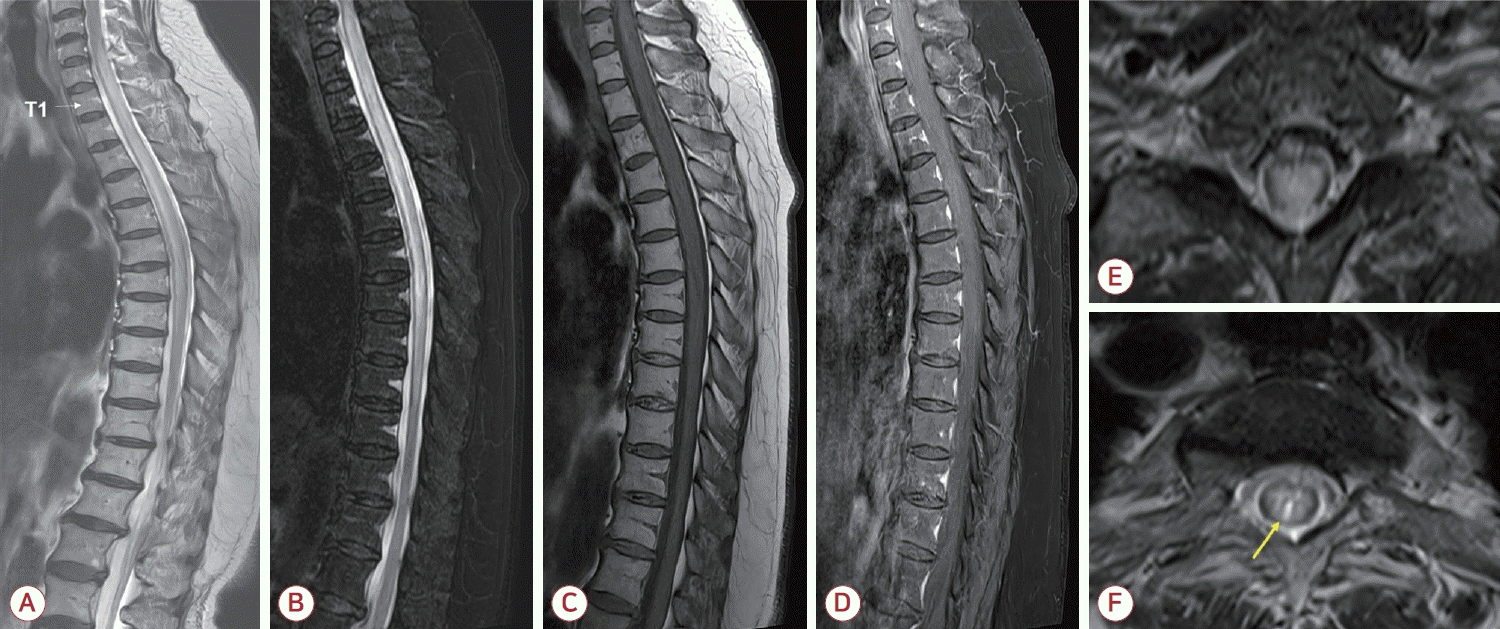

Spine magnetic resonance imaging (MRI) findings of the case patient. (A) Sagittal T2-weighted image of the whole spine demonstrated a longitudinally extensive lesion extending from C6 to T9 (white arrow indicating the level of T1 vertebral body). (B) Fat-suppressed T2-weighted image showed mild cord swelling, and (C) corresponding T1-weighted image revealed subtle hypointensity in the same region. (D) Post-gadolinium T1-weighted image did not demonstrate abnormal enhancement. (E) Axial T2-weighted image at the C7 level and (F) at the T3 level showed extensive hyperintense lesion involving the central gray matter with a focal hyperintense area. In panel (F), a brighter spotty lesion is indicated by a yellow arrow.

척수MRI 검사를 통하여 척수 횡단면을 거의 다 침범하는 경추 6번분절부터 흉추 9번분절에 이르는 세로로 매우 긴 T2 고신호강도와 T1 저신호강도, 척수부종을 확인하였다(Fig.). NMOSD에서 특징적인 brighter spotty lesion (BSL)도 관찰되었으나 조영증강은 없었다. 뇌척수액 분석에서는 백혈구 19/mm3, 적혈구 211/mm3, 단백질 26.1 mg/dL, 포도당 79 mg/dL (혈청 포도당 193 mg/dL)였다. 면역글로불린-G지수는 0.6이었고 올리고클론띠는 음성이었다. 항수초희소돌기아세포당단백질항체(항myelin oligodendrocyte glycoprotein [MOG]항체)는 음성이었다. 항아쿠아포린4항체 검사는 지속적으로 모두 양성(positive [1+] in 1:10; MFIr, 7.65; positive cut-off >1.40)이었다. 척수염 재발로 진단하였고 5일간 고용량(1 g/day) 메틸프레드니솔론 정맥 주사 투여 후 경구 스테로이드로 전환하면서 환자는 재활 병원으로 퇴원하였다. 퇴원 2주 후 외래 진찰 시 EDSS 1.5점으로 약간 호전된 상태였다. 이에 경구 스테로이드 10 mg/day로 유지하면서 아자싸이오프린을 50 mg/day 용량으로 추가하였고 점차 증량하기로 계획하였다.

본 증례의 환자는 67세에 비정형 증상과 짧은 길이의 척수염 병터, 항체 양성을 통해 NMOSD이 처음 진단된 늦은 발병(late-onset) 환자에 속한다. 재발 역시 척수염이었으나 처음의 척수염과는 전혀 다른 영상 특징을 보였는데 10개의 척추분절에 달하는 세로로 매우 긴 병변과 중심회색질을 침범하는 넓은 횡단면 병변, 척수부종, BSL 등은 NMOSD에 부합하는 반면 조영증강은 관찰되지 않았다. 임상 증상도 MRI 병터에서 예상되는 심한 운동장애나 방광기능장애를 보이지 않고 하지 이상 감각으로 인한 보행 불안정성 정도만 호소하였으며 천천히 독립 보행이 가능한 수준으로 비교적 낮은 EDSS를 보여 영상과 임상 소견이 일치하지 않았다.